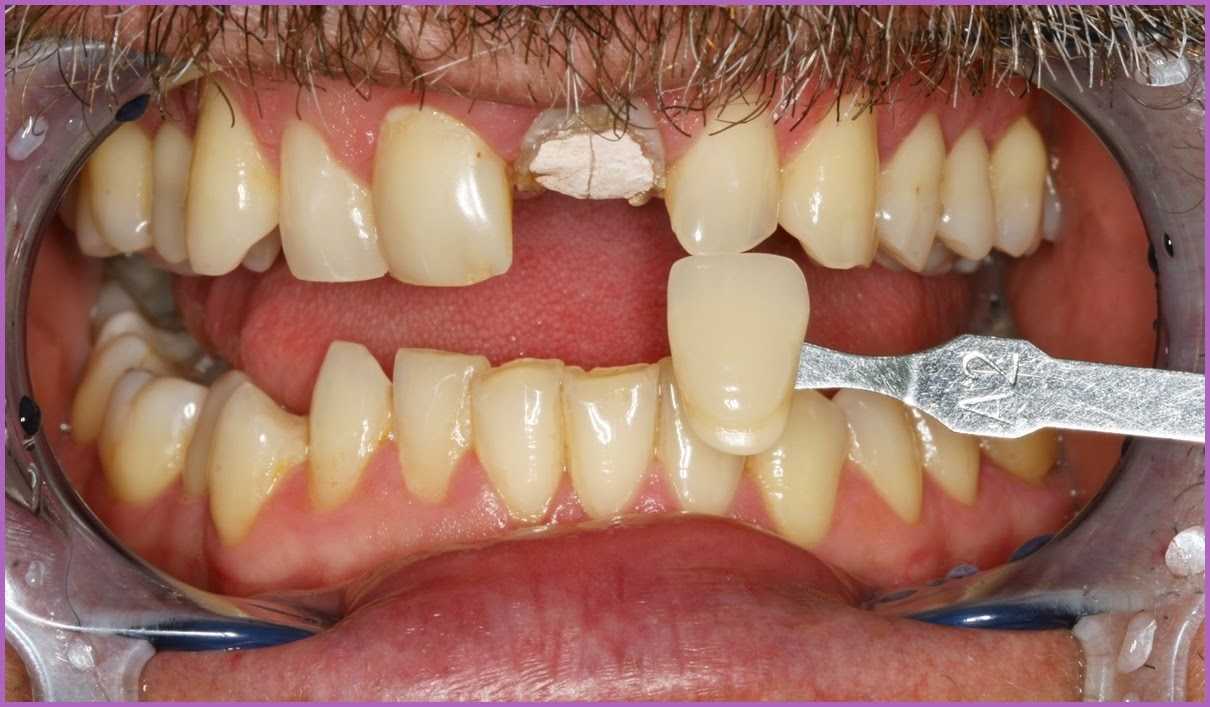

Az Emax korona elkészítésénél a fogpótlás megfelelő esztétikai végeredménye érdekében fogtechnikai laborunk nagyfelbontású fotók alapján dolgozott.